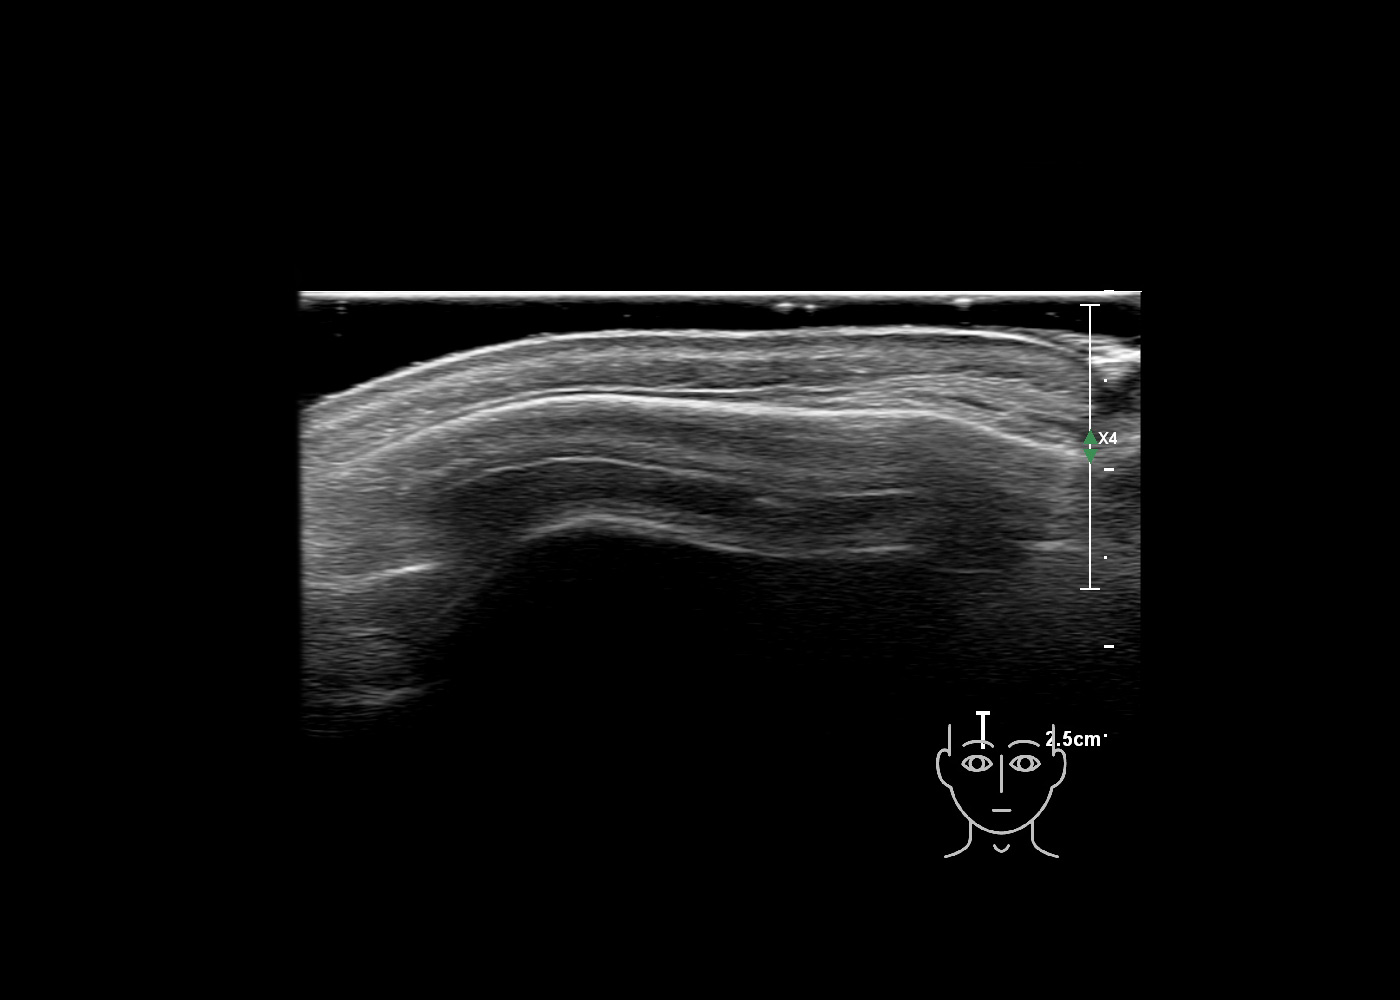

In this section you will learn more about the different layers of the face with the use of ultrasound. When you click on the secondary ultrasound image, you will see the different structures as an overlay. This will help to train yourself to recognize the different layers of the face.

Study the first image to recognize the different layers. If you are sure about the layers, swipe to the second image to view the answer (if applicable).